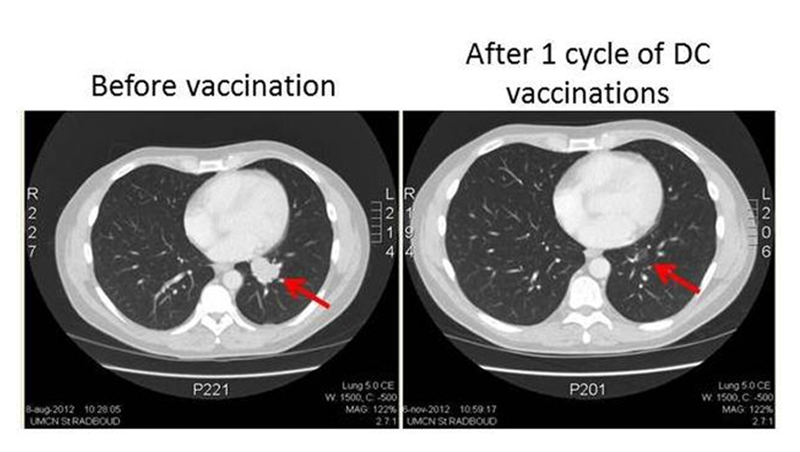

其中一个临床案例尤为振奋:一位肿瘤负荷重、病情进展快的患者,在 1 周期 DC 细胞治疗后,肺部转移瘤通过 CT 扫描清晰可见明显缩小,直观印证了这种疗法的潜力,为局部进展期或转移性黑色素瘤的免疫治疗提供了重要参考。